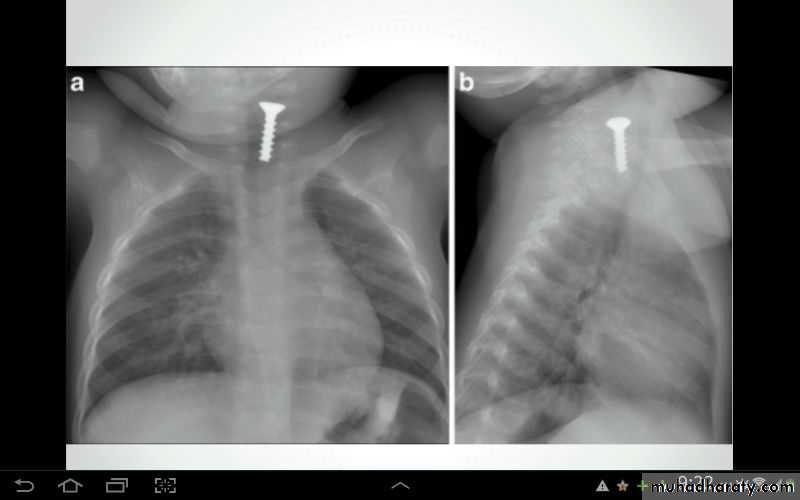

Fall from the 2nd floor